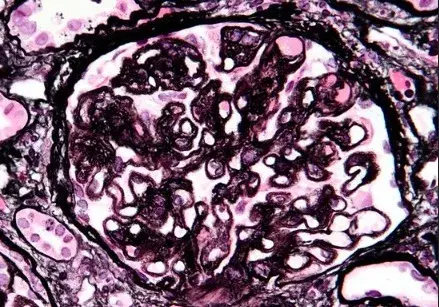

glomerulopatias

nefrite lupica